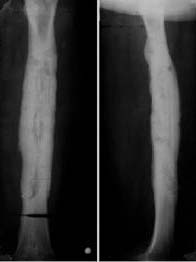

影像学表现:(1)X线平片:早期(3-5天)皮下软组织肿胀,肌间隙模糊;两周后(10-14天始)骨质破坏、骨膜增生(层状),骨膜新生骨包壳形成;部分形成死骨(抗生素广泛应用致少见)。

2周以后:1、骨质疏松:局限;2、骨质破坏为主→骨干;3、骨膜增生:骨包壳;4、骨质坏死:死骨 ;5、轻度骨质增生

(2)CT:能发现细小的破坏区和细小的死骨;(3)MRI:在显示髓腔及软组织受累范围优于平片和CT。充血、水肿、渗出和脓肿在T1WI为低信号, T2WI为高信号,脓腔壁可明显强化。

2、慢性化脓性骨髓炎(慢性骨脓肿(Brodie脓肿):由低毒性 葡萄球菌引起,症状轻。干骺端类圆形 破坏区,有硬化边,偶见小死骨,无骨膜增生,硬化性骨髓炎):增生硬化为主、死骨、瘘管

X线平片与CT:1)病变时愈时发,软组织瘘管形成;(2)骨质破坏的同时,以增生硬化为主;骨干增粗,髓腔闭塞,骨膜增生(形成骨壳),死骨仍存(3)愈合:a、破坏区与死骨消失;b、增生硬化吸收,髓腔沟通。

X线表现:1、骨质增生硬化为主。2、骨质破坏轻。3、有脓腔和死骨。4、骨干增粗、变形。5、髓腔变窄甚至闭塞。

慢性硬化性骨髓炎

X线表现

1、骨质增生硬化

2、骨膜增生,髓腔变窄

3、骨干增粗

慢性骨脓肿(Brodie脓肿):低毒性葡萄球菌引起,症状轻。干骺端类圆形破坏区,有硬化边,无骨膜增生,偶见小死骨。X线表现:1、圆形或卵圆形骨破坏。2、周缘骨硬化。3、少见骨膜反应及死骨。